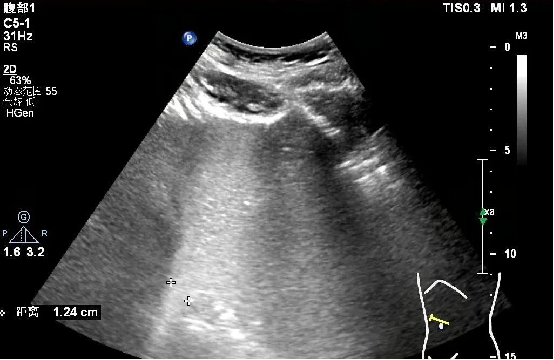

胃造影:

检查所见:贲门上方未见确切囊状扩张,观察贲门5min可见显影剂大于5次从胃反流入食管下段,最大反流束宽约12.4mm。

检查提示:胃食管反流性疾病